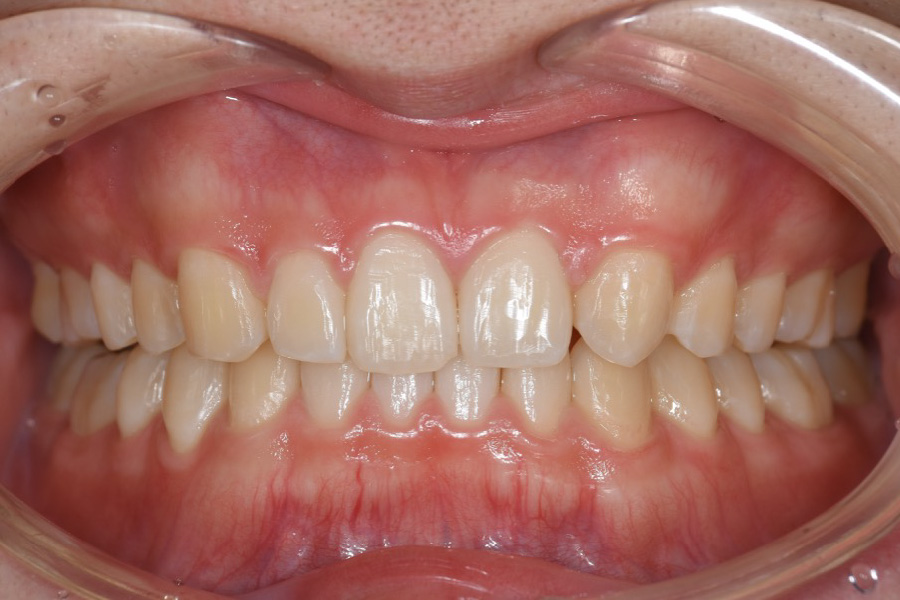

歯並びを治したい

【マウスピース矯正】

かみ合わせが悪い。

前歯がガタついている

- 主訴

- かみ合わせが悪い。前歯がガタついている。

- 期間

- 1年

- 費用

- マウスピース矯正

665,500円(税込)(2025年現在)

- 治療内容

- 目立ちにくいマウスピース矯正(非抜歯矯正)

歯と歯の間に隙間をつくることにより、歯列弓を広げながら治療を行いました。

- 治療に伴うリスク

- ・後戻りする可能性があるのでリテーナーを最低でも矯正期間以上はつけること

・稀にほっぺた、唇、舌などに口内炎や傷ができることがあります